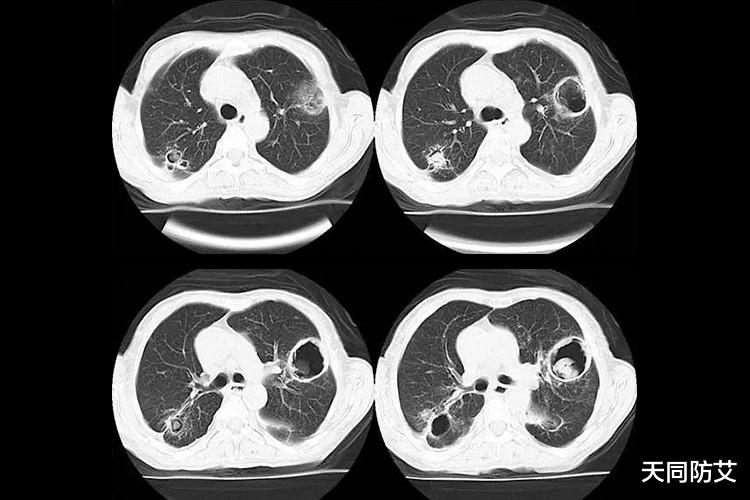

综述指出,侵袭性曲霉病和阻塞性支气管型真菌感染在HIV患者中最为常见。然而,与其他原因(如患有结核病、新冠或流感)导致免疫受损的人相比,这些感染在HIV患者中仍然较为少见。